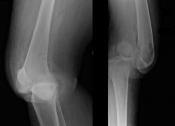

What’s the Diagnosis? Gepost op 14 oktober 201814 oktober 2018 door netwerkvsseh What’s the Diagnosis? @emdaily.cooperhealth.org Dit delen: Delen op X (Opent in een nieuw venster) X Share op Facebook (Opent in een nieuw venster) Facebook Delen op LinkedIn (Opent in een nieuw venster) LinkedIn E-mail een link naar een vriend (Opent in een nieuw venster) E-mail Afdrukken (Opent in een nieuw venster) Print Vind-ik-leuk Aan het laden... Gerelateerd